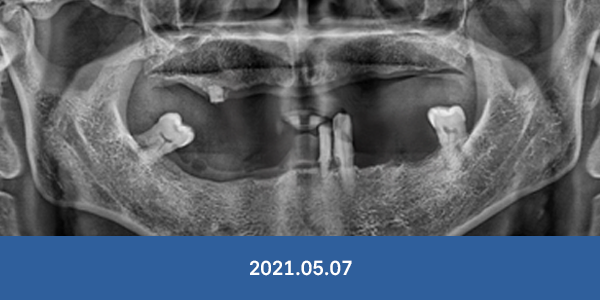

이정웅 대표원장

임플란트 식립 개수

연간 3천개

최근 6년 임플란트 식립개수 누적 1만3천개 돌파

임플란트 수술, 경험이 곧 실력입니다.

임플란트 부작용, 더는 걱정마세요!

개원 이래 대학병원 전원율 0% 달성

※ 서울감동치과에서 실제 수술 받으신 환자분들의 사진입니다.